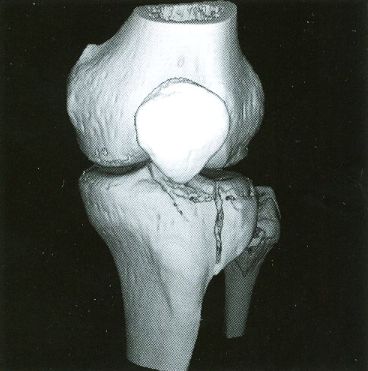

Voxelscope I Screen Shots. First Row: Multiplanar Reformatting; Second Row: 3-D Shaded Surface

The annotation was generated by the software so no more cutting and pasting. :)

The pair of video monitors was the focus of the booth, displaying sequences of skulls and such from real CT datasets like those in the above photos being rotated, sliced, and diced at reasonably rapid update rates. The instructions for performing the operations were captured and recorded but the actual voxel processing was done in real-time based on the stored program. Thus, no one needed to be constantly spinning the trackball, though that could have been arranged upon request. :) The monitors were up high so visitors couldn't get close enough to see how poor the resolution was. :( :) It is believed that VS1 had a microcode-based pipeline running at 10 MHz so that a 128-cube (2,097,152 voxels) could be manipulated at around 5 images per second. The display was 256x256 pixels on a 60 Hz non-interlaced display - double that of VPP. But object space could be configured to be any arbitrary rectangular prism as long as all the data fit into the voxel processor's memory. The photos, above, are typical of the displays at RSNA.